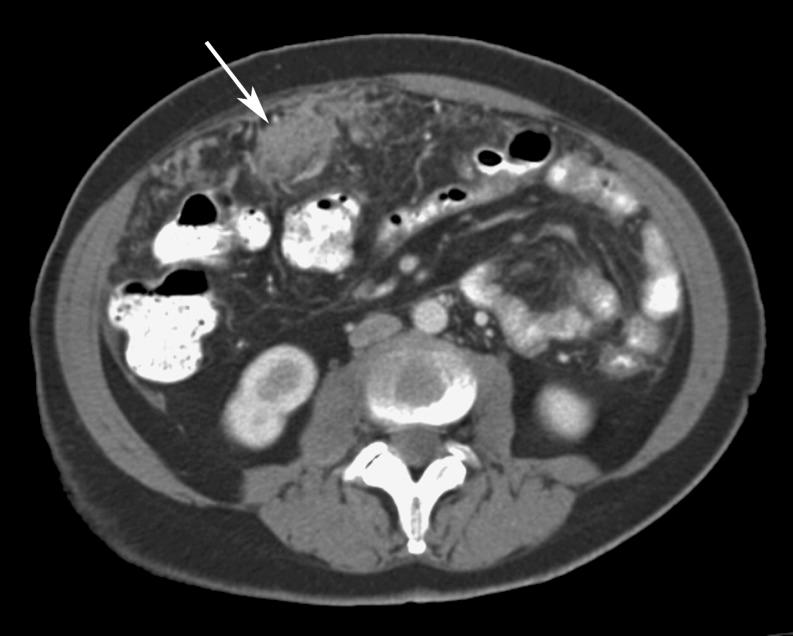

Omental cakes typically are associated with ovarian carcinoma, as this is the most common malignant aetiology. Nonetheless, numerous other neoplasms, as well as infectious and benign processes, can produce omental cakes. METHODS: A broader knowledge of the various causes of omental cakes is valuable diagnostically and to direct appropriate clinical management. RESULTS: We present a spectrum of both common and unusual aetiologies that demonstrate the variable computed tomographic appearances of omental cakes. CONCLUSION: The anatomy and embryology are discussed, as well as the importance of biopsy when the aetiology of omental cakes is uncertain.